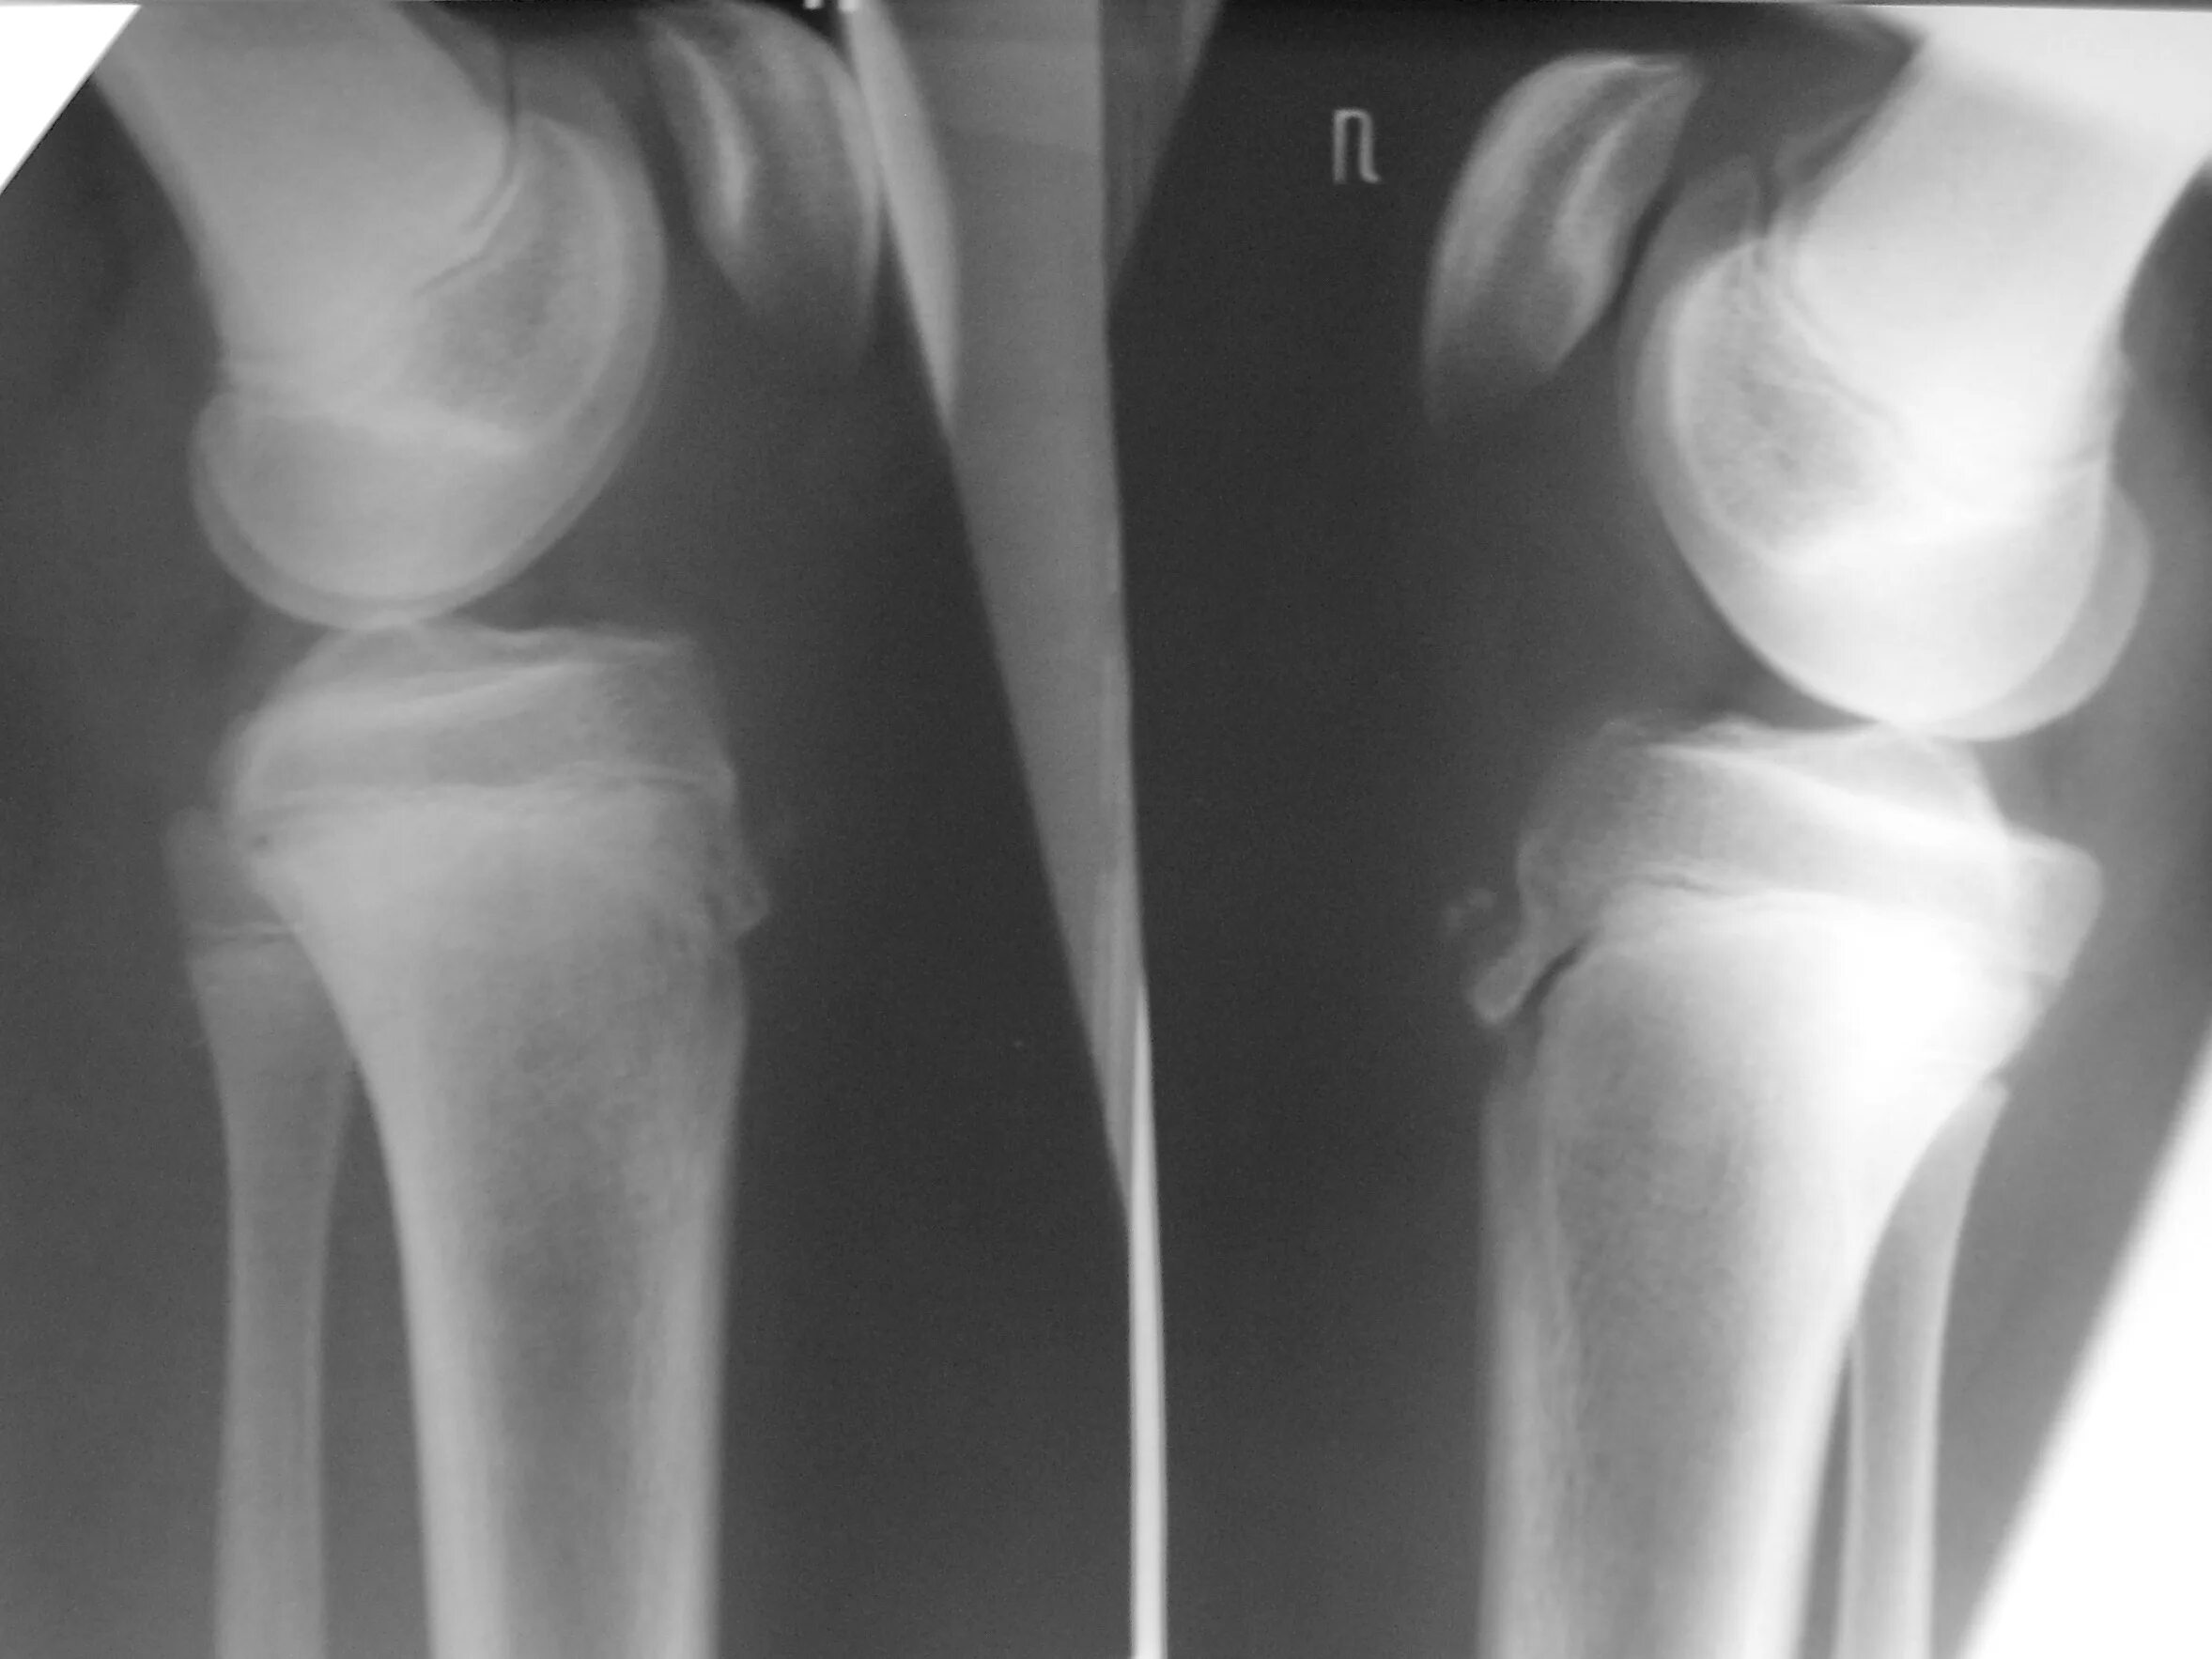

Код мкб шляттера